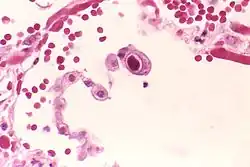

| An MRI showing a transverse myelitis lesion, which is lighter, oval shape at center-right. The patient recovered 3 months later. | |